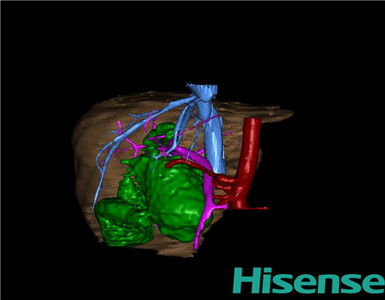

CT结果输入海信CAS系统后行3D重建及手术规划后,于2015-8-15全麻下行“胆总管囊肿切除+胆囊切除+胆总管-空肠吻合术”手术治疗:

术前三维重建及手术方案设计:

将0.625mm双源薄层CT资料的静脉期和动脉期Dicom格式文件导入海信CAS系统。

通过调节窗宽窗位调整CT序号,对肝实质,胆囊,下腔静脉,肿瘤,肝动脉、门静脉及肝静脉等进行三维重建;系统自动计算肝脏体积。

术前手术方案的规划。

完善术前准备后,选择右上腹纵口进入腹腔。结合海信CAS术前规划方案,探查见:胆总管5×3cm大小,胆囊管迂曲,长约10cm。胆总管呈囊状扩张,大小约6×4cm,壁厚。剥离、切除胆囊,游离胆总管,将之横断:①近端即肝总管,剪裁后被吻合用;②远端游离切除囊肿内壁,见壁厚,粘连严重,分离易渗血,游离囊肿至胆总管末端,冲洗后予以结扎缝扎。距treits韧带20cm处横断空肠:①近端与其远端25cm处的空肠侧壁行端侧双层吻合,吻合口通畅;②远端断端封闭,其侧壁剪开,并经横结肠后提至肝门处,与剪裁的肝总管行端侧双层吻合。缝合修补胆囊床及系膜裂孔,防止止血纱布2块,肝门部放置橡胶引流管一根。温盐水冲洗腹腔。检查无活动性出血,清点纱布器械无误,依次缝合腹壁各层。术后胆囊标本家属过目,送检病理。手术时手术者可开启Hisense CAS系统手势控制功能,对胆囊周围血管、组织的解剖结构进行实时、全方观察、评估,起到术中导航作用。

术前三维重建:

重建图片